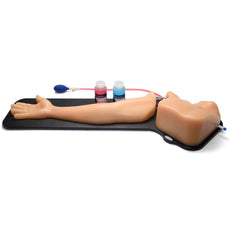

Branched 4 Vessel Ultrasound Training Block Model

Blue Phantom Select Series Branched 4 Vessel vascular access ultrasound training model is an excellent training phantom to help clinicians develop, practice and maintain the skills necessary for ultrasound guided venous access and arterial access procedures. This lightweight model is easily portable for travel and training where you want, when you want. Excellent for clinicians beginning to use ultrasound as well as more advanced users seeking more challenging vascular access insertion technique training. The branched vessels offer multiple training opportunities; independent linear vessels for initial training in addition to multiple overlapping branched vessels for more advanced ultrasound training.Extremely realistic and durable.

Blue Phantom is committed to providing the highest quality ultrasound training models available anywhere. This ultra-durable medical ultrasound model, offers a cost effective solution for clinicians of all experience levels. Constructed using Blue Phantom’s patented ultra-durable simulated tissue, this model matches the acoustic characteristic of human tissue. Clinicians can repeatedly utilize this training aid without the high costs of replacing disposable parts. Blue Phantom’s 4 Vessel model can be used thousands of times without requiring replacement.

This medical simulation trainer will provide excellent results using any ultrasound imaging system configured with the appropriate transducer (recommended ultrasound transducer; high frequency linear array ultrasound probe 5.0 – 12 MHz). This ultrasound phantom model is excellent for specialties including anesthesiology (anaesthesiology), emergency medicine, radiology, nursing, PICC nursing, surgery, ultrasound training programs, simulation centers, surgical skills centers, medical education facilities, and ultrasound manufacturers for ultrasound education and demonstrations. Excellent for both beginners and more advanced used to develop skills associated with arterial access , vein cannulation, venipuncture, central line placement and PICC lines.

- Size 7” x 5” x 2.5” (17cm x 13cm x 6cm) (L x W x H)

- Weight 3.0 lbs. (1.3 Kg.)